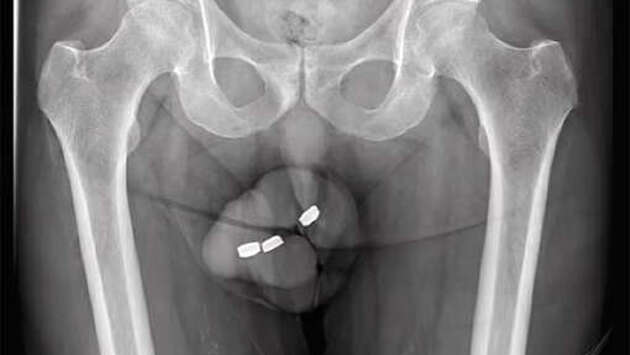

Врачам из Австралии пришлось удалить часть пениса мужчины из-за некроза. Он возник после того, как 73-летний мужчина засунул в уретру три сантиметровых батарейки. Об этом сообщает Daily Mail. Неназванный 73-летний житель Австралии обратился в больницу с жалобами на боль и трудности с мочеиспусканием. Он признался врачам, что за сутки до этого засунул в уретру три батарейки. Мужчина делал это не впервые, и в прошлом у него никогда не было проблем с их извлечением. Однако в этот раз он лишь протолкнул их глубже. Осмотр показал, что уретра почернела, а во время операции под общей анестезией врачи выявили некроз и ожоги. Хирурги извлекли три батарейки диаметром 1,3 см. Через десять дней мужчина вернулся в больницу с жалобами на отек и выделения из уретры. Врачам пришлось провести еще одну операцию, во время которой они удалили часть пениса из-за некроза. Мужчине также установили катетер, помогавший ему мочиться. Спустя две недели его заменили надлобковым катетером (цистостомой). Это устройство нужно менять каждые 4-12 недель. Оно представляет собой трубку, которую через отверстие в брюшной полости вводят непосредственно в мочевой пузырь.